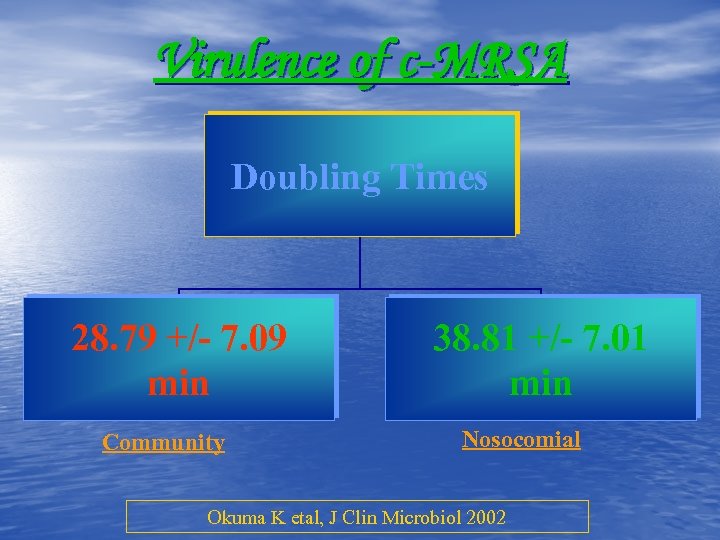

Virulence of c-MRSA Doubling Times 28. 79 +/- 7. 09 min Community 38. 81 +/- 7. 01 min Nosocomial Okuma K etal, J Clin Microbiol 2002

Virulence of c-MRSA Doubling Times 28. 79 +/- 7. 09 min Community 38. 81 +/- 7. 01 min Nosocomial Okuma K etal, J Clin Microbiol 2002